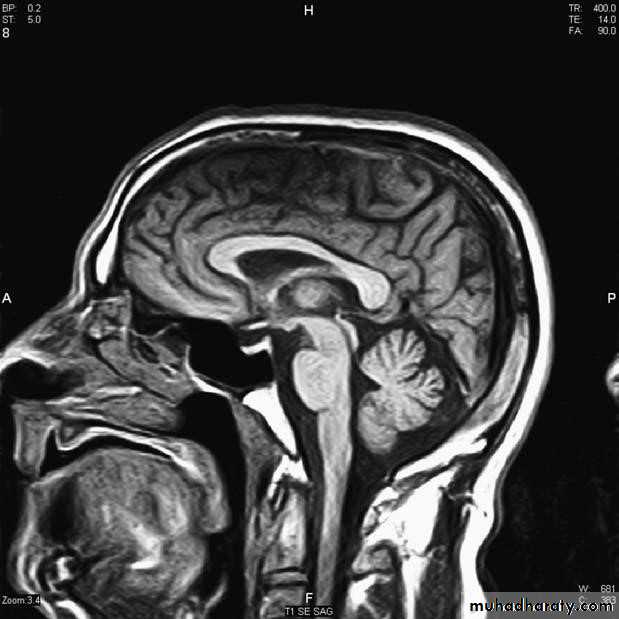

Magnetic resonance imaging: MRI

▪ The hydrogen nucleus is a proton whose electrical charge creates a local electrical field. These protons are aligned by sudden strong magnetic impulses. Protons are then imaged with radiofrequency waves at right angles to their alignment. The protons resonate and spin, then revert to their normal alignment. As they do so, images are made at different phases of relaxation, known as T1, T2, T2 'STIR', diffusion-weighted imaging (DWI) and other sequences. Gadolinium is used as an intravenous contrast medium .Advantages of MRI

▪ High quality soft tissue images .▪ MR distinguishes between brain white and grey matter .

▪ Pituitary imaging .

▪ MRI has greater resolution than CT (around 0.5 cm(

▪ Useful for posterior fossa and temporal lobe .